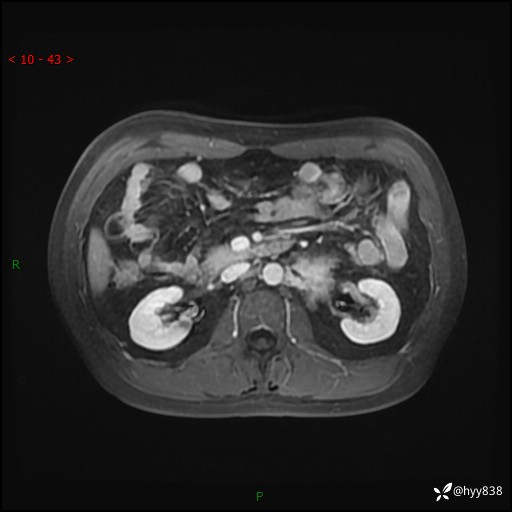

MRI增强